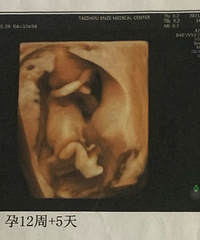

预产期:2022.08.30建卡医院:台州妇女儿童医院产检医院:台州妇女儿童医院胎宝宝小名:未定生产医院:台州妇女儿童医院B超照片/孕期相关照片一张: